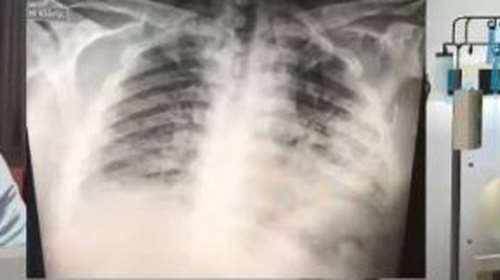

Σοκαριστικό: Έτσι είναι οι πνεύμονες ενός ασθενούς με κορονοϊό [Βίντεο]

Ανεπανόρθωτες οι βλάβες που υφίσταται ο ανθρώπινος οργανισμός από τον κορονοϊό